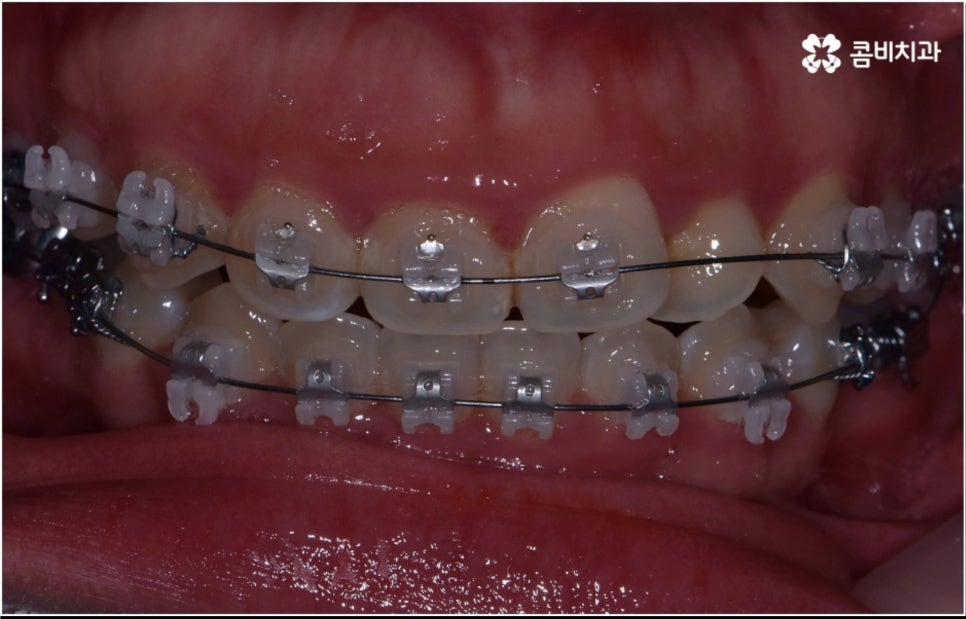

성인 치아교정 기간 이 길어지면 생활상 또는 업무상 활발한 대인 관계를 맺고 있으신 분들의 경우 교정 장치가 눈에 띄는 문제 때문에 불편함을 느끼실 수 있어요. 하지만 최근 관련 기술의 발달로 장치들 역시 심미성이 뛰어난 것들이 많이 개발되었으며 선택의 폭이 넓어졌기 때문에 치료 과정 중에도 이러한 부담감을 줄이고 보다 만족도를 높일 수 있습니다.

치아 색상의 세라믹 브라켓을 이용하는 장치들은 예전 메탈 장치 보다 심미성이 훨씬 보완되었으며, 치아 뒤쪽에 장치를 부착하여 아예 눈에 띄지 않는 설측교정장치나 언뜻 보면 티가 잘 나지 않는 얇고 투명한 특수 강화 플라스틱을 이용하는 투명교정장치를 이용하면 교정을 하고 있다고 본인이 말을 하지 않으면 잘 모를 정도로 심미성이 뛰어나기 때문에 각 장치들의 소재와 특성, 장단점에 대해서 잘 알아보고 신중한 선택을 하는 것이 중요하다고 할 수 있어요.